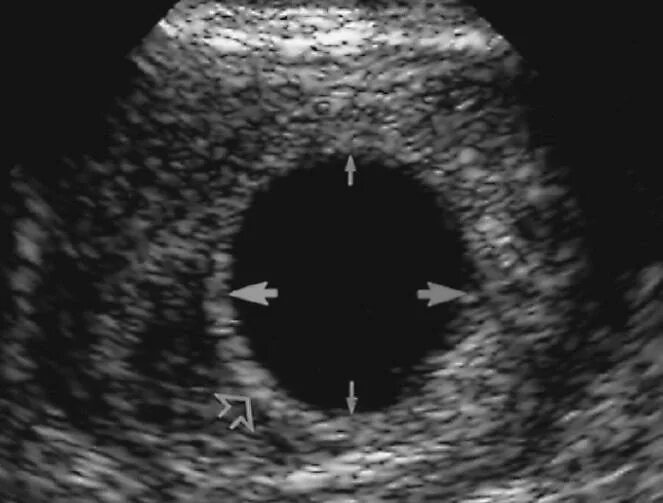

Анэмбриония – пустое плодное яйцо. плодное яйцо 7 мм желточный мешок 6 мм. снимок узи пустого плодного яйца.

Узи плодное яйцо 6 недель. плодное яйцо на 6 неделе беременности узи. пустое плодное яйцо на 6 неделе. анэмбриония – пустое плодное яйцо.

Анэмбриония – пустое плодное яйцо. неразвивающаяся беременность узи. пустое плодное яйцо на узи. узи 8 недель беременности анэмбриония.

Пустое плодное яйцо на узи. анэмбриония – пустое плодное яйцо. плодное яйцо на узи на ранних сроках 2 недели. ложное плодное яйцо на узи.